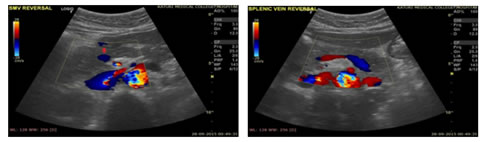

Figure 1: USG Axial image showing Dilated Portal Vein; Figure 2: USG Axial image showing Loss of Respiratory variations in Portal Vein diameter; Figure 3: Colour Doppler showing Flow reversal in Splenic vein; Figure 4: Colour Doppler Axial image: Flow reversal in SMV shown by arrow; Figure 5: USG Axial image showing dampened flow in Portal vein; Figure 6: HRUS image showing Nodular liver surface in cirrhosis

Figure 7: Spectral Doppler USG image: Showing Biphasic flow in Splenic vein; Figure 8: Gray scale and Colour Doppler USG image: Showing Cavernomatous transformation of Portal vein; Figure 9: Gray scale and Colour Doppler USG image; Figure 10: Showing Dilated Coronary vein with Hepatofugal flow; Figure 11: Gray scale and Colour Doppler USG image: Showing GEJ collaterals; Figure 12: Gray scale and Colour Doppler USG image: Showing Lienorenal collaterals; Figure 13: Gray scale and Colour Doppler USG image: Showing Recannalised Paraumbilical vein with hepatofugal flow; Figure 14: Colour Doppler USG image: Showing Absent Colour flow in Portal vein due to Thrombosis